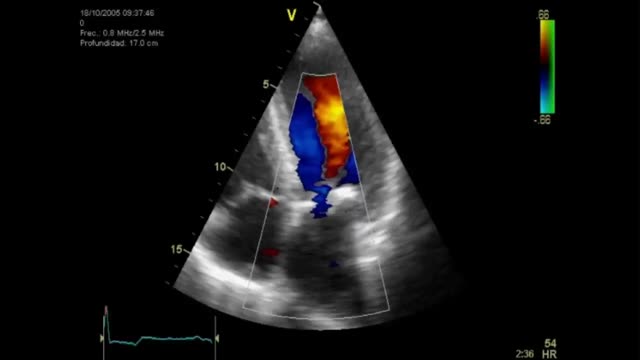

Uno de los cuadros clínicos más difíciles de manejar en el PC es la insuficiencia mitral que se produce por un movimiento anómalo de la valva anterior (SAM), generando un gradiente de presión en el TSVI o mesoventricular, arrastrando y succionando la valva anterior mitral (fig. 3). Debe sospecharse en casos con hipertrofia concéntrica, miectomía o implante de prótesis mitral con postes grandes que se dirigen hacia el TSVI, estados de hipovolemia y/o necesidad de soporte vasoactivo ascendente sin respuesta tensional apropiada.

PC de bypass coronario en paciente con hipertrofia del VI concéntrica: obstrucción dinámica TSVI por exceso de soporte inotrópico e hipovolemia postoperatoria, generando insuficiencia mitral severa por movimiento septal anterior (SAM). Obsérvese el flujo de aceleración progresiva por Doppler continuo.